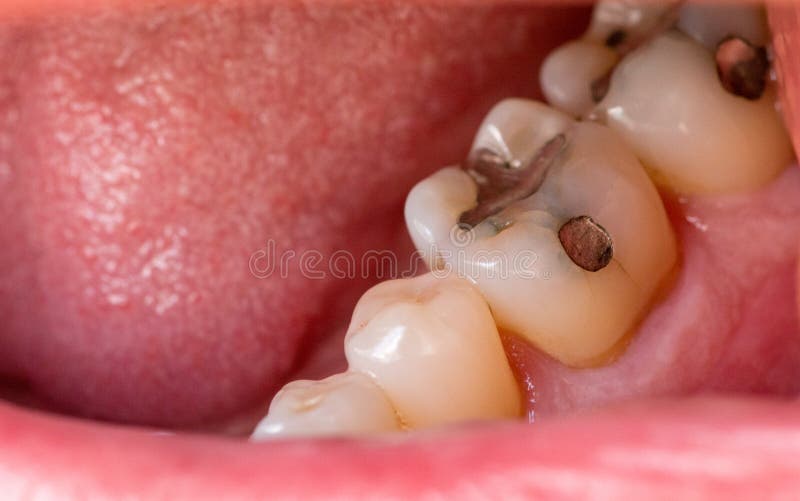

A filling that has fallen out will often look dark in the hole left behind. I dont know if I have swallowed any or not.

Amalgam filling fell out. For example amalgam fillings and gold fillings are much less brittle than composite and glass ionomer fillings and so are less susceptible to damage from chewing. Beyond their risk of breaking non-metal fillings also tend to lose their binding to the tooth and fall out earlier. A filling that has fallen out will often look dark in the hole left behind.

This may be decay or stain from an old metal amalgam filling. If it is a front tooth saving the filling may be helpful for your dentist. For example amalgam fillings and gold fillings are much less brittle than composite and glass ionomer fillings and so are less susceptible to damage from chewing.